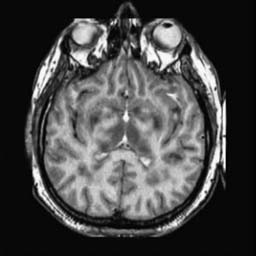

To demonstrate the effectiveness and efficiency of the proposed image fusion method , we conduct a set of comparative experiments on three image datasets. The first is composed by 8 pairs of multi-modal medical images and the second one contains 15 pairs of multi-focus gray or color natural images. These two datasets are often used in many related papers and some examples are shown in Figure 3(a) and Figure 3(b). The third one is a new multi-focus cervical cell image dataset collected by ourselves, which consists of 15 groups of color images and each group contains a series of multi-focus cervix cell images with size of or , etc. Some source examples are shown in Figure 3(c). Our source code implemented in C++ along with the new multi-focus cervical cell image dataset is available online.

We first evaluate the performance of the proposed method under varying total number of octaves and number of layers sampled per octave. The fused images of a pair of multi-modal medical images with different and are shown in Figure 4. In this example, on the one hand, when only 1 or 2 octaves are involved in constructing the DoG pyramid, the fused images fail to keep the integrity information of large size objects (e.g. eyeballs), while by increasing the value of , the integrity information of eyeballs is preserved. On the other hand, although not as significant as the increase of octave numbers , the fused image can contain more details by the increase of layer numbers . The corresponding objective quality metrics are shown in Figure 5. As shown in Figure 5(a), most of the metric values are improved as the number of octaves increases with the fixed layer numbers 3 in the global tendency and each of them tends to be stable when the number of octaves is 5. To get a relatively good quality from Figure 5(b), we can notice that some of the metric values can get a good performance when the number of layers is 3, such as the MI, SSIM, QI and VIF, though there are only a little change of all the metric values by increasing the number of layers with the fixed octave numbers 5. Because it will result in more computation burden with the increase of the value and , and for different kinds of source images, there are different performance with the diverse parameter settings. To get a trade-off between them in our experiments, we set for the multi-modal dataset, for the natural datasets and for the multi-focus cell dataset, respectively.

Figure 6 shows the fused images obtained by different methods with the multi-modal source images shown in Figure 3(a). As shown in these figures, the proposed method can produce images which preserve the complementary information of different source images well. Moreover, due to the scale-invariant structure saliency selection, our method can keep the integrity information of large size objects and the visual details simultaneously. Although the fused image generated by other methods can also capture the details to some extent, all of them fail to keep the integrity information of large size objects such as the eyeballs. Furthermore, from Figure 6(k)-6(t), the DTCWT, GFF, IM and NSCT methods may decrease the brightness and contrast while the proposed method can preserve these features and details without producing visible artifacts and brightness distortions.